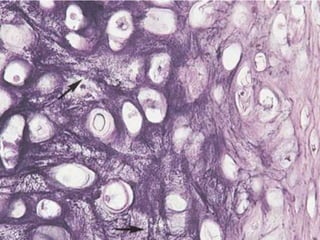

Este documento presenta imágenes microscópicas de diferentes tipos de tejidos y estructuras celulares teñidas con varios métodos histológicos. Incluye fotografías que muestran fibras de colágeno, elásticas y reticulares en diversos órganos, así como membranas basales y células especializadas de órganos como riñones, glándulas mamarias y próstata. El propósito es demostrar la aplicación de técnicas histológicas para visualizar componentes celulares y tej